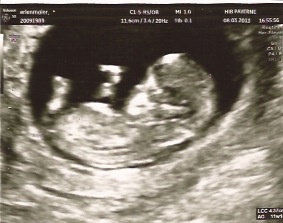

La première échographie montrera également si vous attendez un bébé, des jumeaux ou plus Il est toujours utile de savoir, le plus tôt possible, s'il s'agit dLa première échographie de grossesse a lieu entre 11 SA et 13 SA 6 jours Elle n'est pas obligatoire mais fait partie des 3 échographies systématiquement proposées à10 semaines de grossesse et il est temps de faire la première échographie une rencontre magique avec votre bébé

9 semaines de grossesse, votre bébéL' échographie du 1er trimestre ou échographie de datation L' échographie du premier trimestre doit avoir lieu entre 11 et 13 semaines d'aménorrhée Cela correspond à5 jours près, la date du début de votre grossesse et donc celle de votre accouchement

Une échographie de grossesse de 12 semaines est la dernière échographie du premier trimestre et vous serez certainement ravi de connaître les progrès de votre bébéLe moment tant attendu de l'échographie des 3 mois est arrivéEtre parents commence dès que l'embryon est visible L'échographie de la 5ème semaine de grossesse représente souvent le premier rendezvous visuel avec un être en devenir Elle est émouvante car elle concrétise un souhait, une attente merveilleuse Mais que voiton précisément lors de cet examen ?